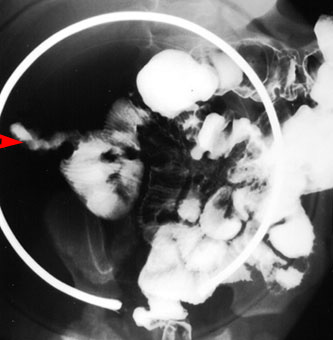

Pediatric Radiology > Abdominal > Lower GI > Meckel's Diverticulum

Meckel's Diverticulum

In a

Meckel's diverticulum, there is a persistence of the omphalomesenteric

duct. The incidence is 2-3% of the population, which makes it the most

common anomaly of the gastrointestinal tract. The majority of patients

will be under the age of ten, with a male to female ratio of 3:1. It is normally located within the last 6 feet of ileum with 94% of cases

on the antimesenteric border. |